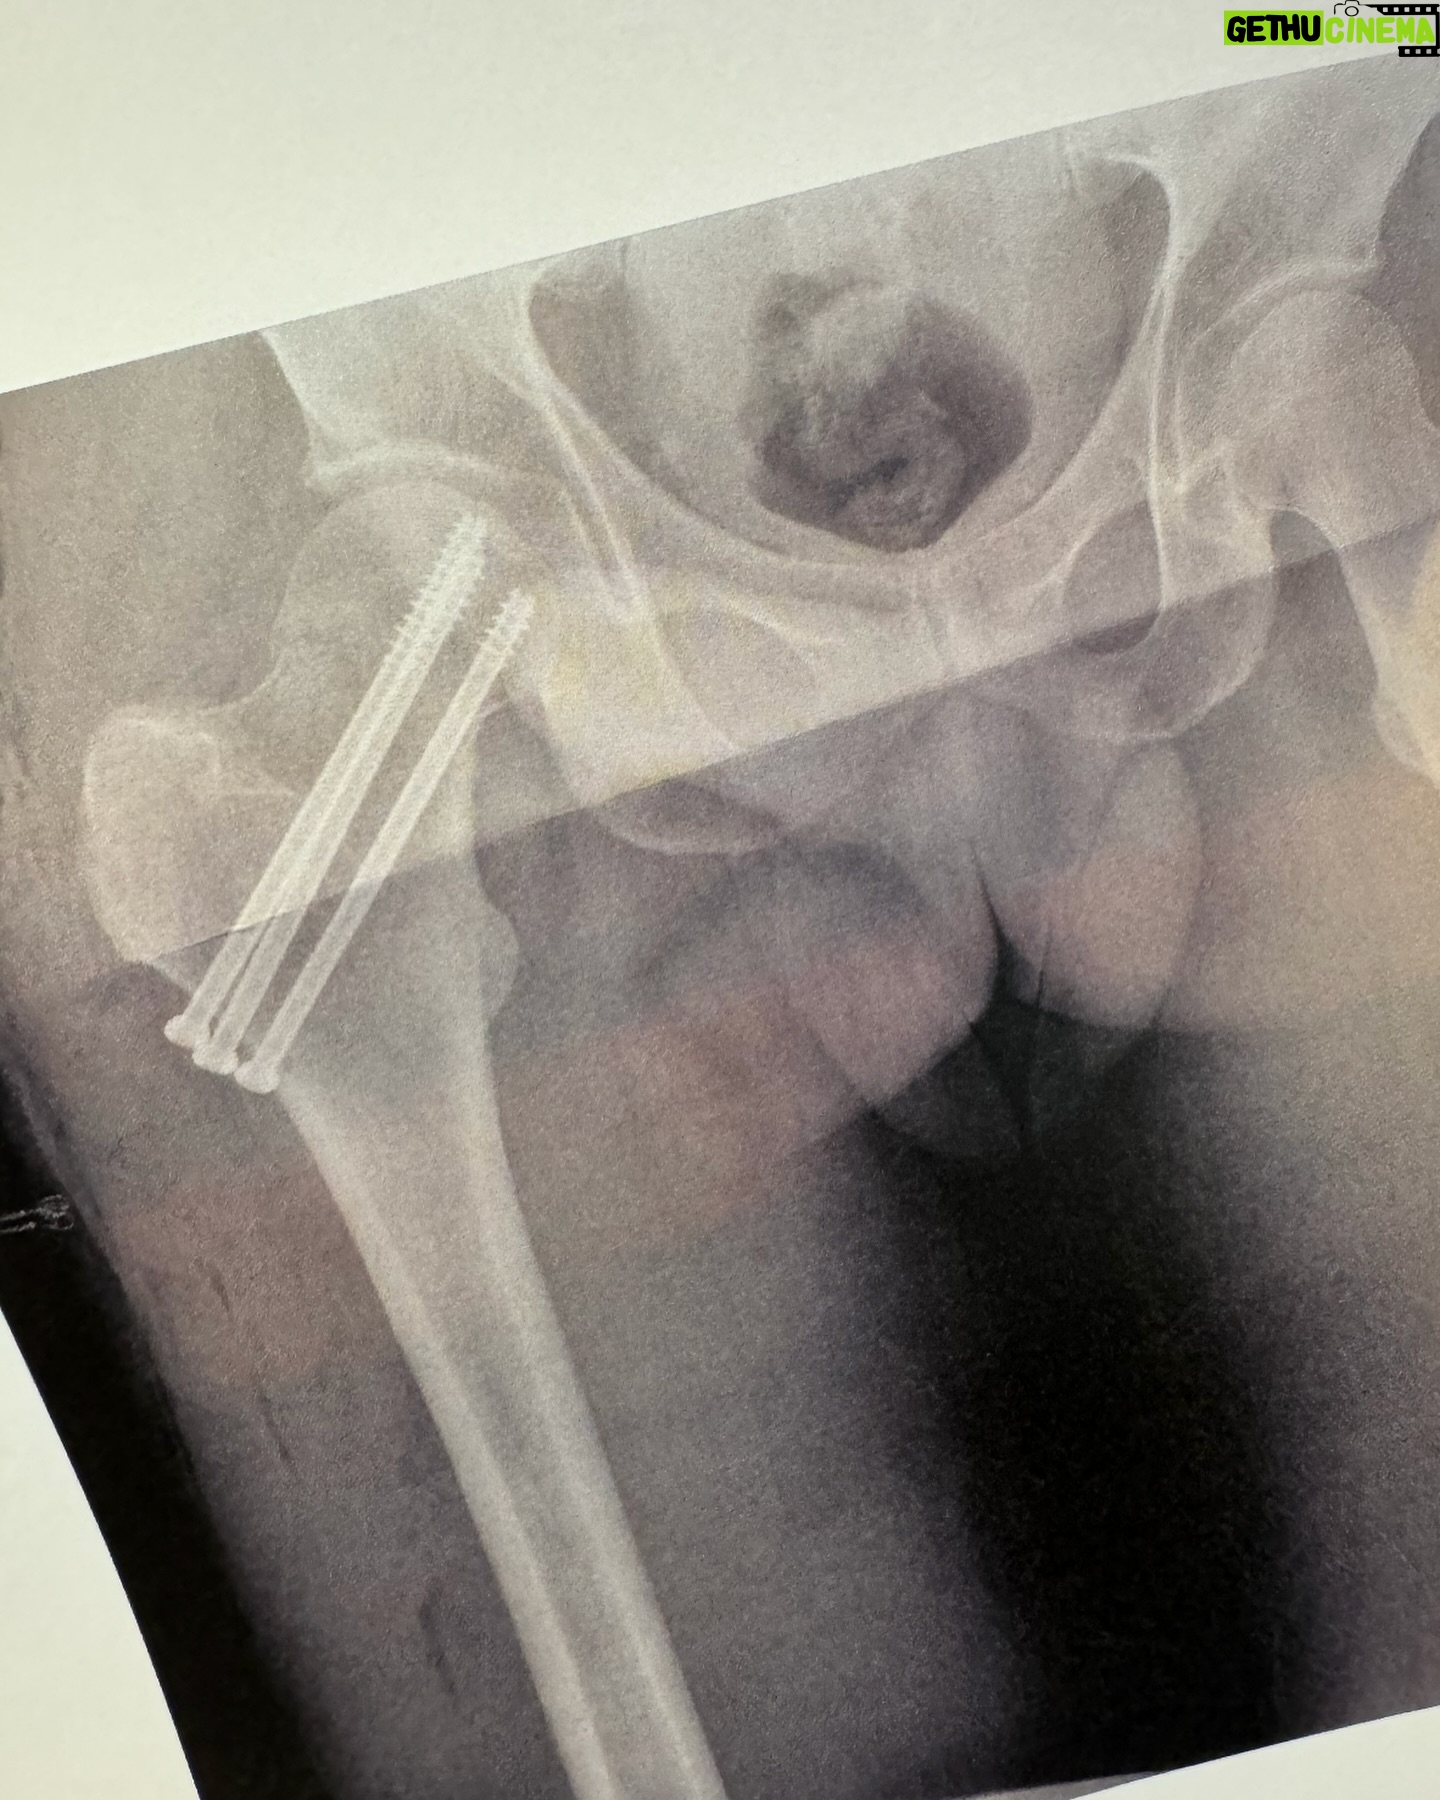

Caption : Мотивационный пост про то, как не унывать! Итак, полгода назад я, катаясь на горных лыжах, упал и оторвал руку (разрывов акромиально-ключичного сочленения). Меня спас добрый доктор, который ловко пришил руку на место и я начал восстанавливаться. Казалось бы, что может пойти не так? Отличная погода, велосипед, я решаю перед завтраком сделать тренировку 50 км. Единственное, что смущало – это сильный ветер. Точнее он меня не смущал, но как сейчас понимаю, зря. Первые 25 км он был встречный, что не позволяло держать среднюю скорость выше 25 км/ч. Но вот на обратном пути я решил оторваться! Насвистывая песенку кота Леопольда, я устремился к финишу вместе с ветром. Кручу, кручу, кручу педали, кручу, С горы, с горы, с горы как птица лечу. Спешу, спешу, спешу, спешу налегке Навстречу радуге – дуге. В какой-то момент я потерял концентрацию и полетел на асфальт. Что стало причиной падения я так и не понял. Возможно слишком высокая скорость, может на дороге что-то было, возможно виноват Леопольд с его радугой (как мы знаем, все проблемы из-за радуги). Вначале я ничего не понял. Боли не было. Попытался отползти с дороги, но тело не слушалось и я болтался на асфальте как червяк. К счастью, остановились несколько машин. Добрые люди помогли мне подняться и отвезли в ближайшую больницу. Уже в машине я понял, что с ногой явно что-то не так. Любое движение вызывало адскую боль! Меня отвезли на рентген и диагноз был неутешительный. Я сломал шейку бедра, а еще кости руки в районе плеча, того самого, что мне чинили год назад. В общем, нужна была срочная операция! Меня очень ловко перегрузили на красивую кроватку и повезли в операционную. Перед тем, как вырубить меня, анастезиолог спросила, о чем я думаю. Я сказал, что переживаю, что не завещал свои органы в случае смерти другим пациентам и попросил считать это моей последней волей. Девушка сказала, что я дурак и надо думать о чем-то приятном, я переключился на песенку кота Леопольда и отключился. Очнулся на удивление в роскошном настроение! Не знаю, что мне вкололи, но я был абсолютно счастлив, у меня ничего не болело, если не шевелиться. Если раньше я не мог пользоваться правой рукой, то теперь еще и правой ногой! 👇🏻Likes : 94170

Caption : Мотивационный пост про то, как не унывать! Итак, полгода назад я, катаясь на горных лыжах, упал и оторвал руку (разрывов акромиально-ключичного сочленения). Меня спас добрый доктор, который ловко пришил руку на место и я начал восстанавливаться. Казалось бы, что может пойти не так? Отличная погода, велосипед, я решаю перед завтраком сделать тренировку 50 км. Единственное, что смущало – это сильный ветер. Точнее он меня не смущал, но как сейчас понимаю, зря. Первые 25 км он был встречный, что не позволяло держать среднюю скорость выше 25 км/ч. Но вот на обратном пути я решил оторваться! Насвистывая песенку кота Леопольда, я устремился к финишу вместе с ветром. Кручу, кручу, кручу педали, кручу, С горы, с горы, с горы как птица лечу. Спешу, спешу, спешу, спешу налегке Навстречу радуге – дуге. В какой-то момент я потерял концентрацию и полетел на асфальт. Что стало причиной падения я так и не понял. Возможно слишком высокая скорость, может на дороге что-то было, возможно виноват Леопольд с его радугой (как мы знаем, все проблемы из-за радуги). Вначале я ничего не понял. Боли не было. Попытался отползти с дороги, но тело не слушалось и я болтался на асфальте как червяк. К счастью, остановились несколько машин. Добрые люди помогли мне подняться и отвезли в ближайшую больницу. Уже в машине я понял, что с ногой явно что-то не так. Любое движение вызывало адскую боль! Меня отвезли на рентген и диагноз был неутешительный. Я сломал шейку бедра, а еще кости руки в районе плеча, того самого, что мне чинили год назад. В общем, нужна была срочная операция! Меня очень ловко перегрузили на красивую кроватку и повезли в операционную. Перед тем, как вырубить меня, анастезиолог спросила, о чем я думаю. Я сказал, что переживаю, что не завещал свои органы в случае смерти другим пациентам и попросил считать это моей последней волей. Девушка сказала, что я дурак и надо думать о чем-то приятном, я переключился на песенку кота Леопольда и отключился. Очнулся на удивление в роскошном настроение! Не знаю, что мне вкололи, но я был абсолютно счастлив, у меня ничего не болело, если не шевелиться. Если раньше я не мог пользоваться правой рукой, то теперь еще и правой ногой! 👇🏻Likes : 94170

Caption : Мотивационный пост про то, как не унывать! Итак, полгода назад я, катаясь на горных лыжах, упал и оторвал руку (разрывов акромиально-ключичного сочленения). Меня спас добрый доктор, который ловко пришил руку на место и я начал восстанавливаться. Казалось бы, что может пойти не так? Отличная погода, велосипед, я решаю перед завтраком сделать тренировку 50 км. Единственное, что смущало – это сильный ветер. Точнее он меня не смущал, но как сейчас понимаю, зря. Первые 25 км он был встречный, что не позволяло держать среднюю скорость выше 25 км/ч. Но вот на обратном пути я решил оторваться! Насвистывая песенку кота Леопольда, я устремился к финишу вместе с ветром. Кручу, кручу, кручу педали, кручу, С горы, с горы, с горы как птица лечу. Спешу, спешу, спешу, спешу налегке Навстречу радуге – дуге. В какой-то момент я потерял концентрацию и полетел на асфальт. Что стало причиной падения я так и не понял. Возможно слишком высокая скорость, может на дороге что-то было, возможно виноват Леопольд с его радугой (как мы знаем, все проблемы из-за радуги). Вначале я ничего не понял. Боли не было. Попытался отползти с дороги, но тело не слушалось и я болтался на асфальте как червяк. К счастью, остановились несколько машин. Добрые люди помогли мне подняться и отвезли в ближайшую больницу. Уже в машине я понял, что с ногой явно что-то не так. Любое движение вызывало адскую боль! Меня отвезли на рентген и диагноз был неутешительный. Я сломал шейку бедра, а еще кости руки в районе плеча, того самого, что мне чинили год назад. В общем, нужна была срочная операция! Меня очень ловко перегрузили на красивую кроватку и повезли в операционную. Перед тем, как вырубить меня, анастезиолог спросила, о чем я думаю. Я сказал, что переживаю, что не завещал свои органы в случае смерти другим пациентам и попросил считать это моей последней волей. Девушка сказала, что я дурак и надо думать о чем-то приятном, я переключился на песенку кота Леопольда и отключился. Очнулся на удивление в роскошном настроение! Не знаю, что мне вкололи, но я был абсолютно счастлив, у меня ничего не болело, если не шевелиться. Если раньше я не мог пользоваться правой рукой, то теперь еще и правой ногой! 👇🏻Likes : 94170

Caption : Мотивационный пост про то, как не унывать! Итак, полгода назад я, катаясь на горных лыжах, упал и оторвал руку (разрывов акромиально-ключичного сочленения). Меня спас добрый доктор, который ловко пришил руку на место и я начал восстанавливаться. Казалось бы, что может пойти не так? Отличная погода, велосипед, я решаю перед завтраком сделать тренировку 50 км. Единственное, что смущало – это сильный ветер. Точнее он меня не смущал, но как сейчас понимаю, зря. Первые 25 км он был встречный, что не позволяло держать среднюю скорость выше 25 км/ч. Но вот на обратном пути я решил оторваться! Насвистывая песенку кота Леопольда, я устремился к финишу вместе с ветром. Кручу, кручу, кручу педали, кручу, С горы, с горы, с горы как птица лечу. Спешу, спешу, спешу, спешу налегке Навстречу радуге – дуге. В какой-то момент я потерял концентрацию и полетел на асфальт. Что стало причиной падения я так и не понял. Возможно слишком высокая скорость, может на дороге что-то было, возможно виноват Леопольд с его радугой (как мы знаем, все проблемы из-за радуги). Вначале я ничего не понял. Боли не было. Попытался отползти с дороги, но тело не слушалось и я болтался на асфальте как червяк. К счастью, остановились несколько машин. Добрые люди помогли мне подняться и отвезли в ближайшую больницу. Уже в машине я понял, что с ногой явно что-то не так. Любое движение вызывало адскую боль! Меня отвезли на рентген и диагноз был неутешительный. Я сломал шейку бедра, а еще кости руки в районе плеча, того самого, что мне чинили год назад. В общем, нужна была срочная операция! Меня очень ловко перегрузили на красивую кроватку и повезли в операционную. Перед тем, как вырубить меня, анастезиолог спросила, о чем я думаю. Я сказал, что переживаю, что не завещал свои органы в случае смерти другим пациентам и попросил считать это моей последней волей. Девушка сказала, что я дурак и надо думать о чем-то приятном, я переключился на песенку кота Леопольда и отключился. Очнулся на удивление в роскошном настроение! Не знаю, что мне вкололи, но я был абсолютно счастлив, у меня ничего не болело, если не шевелиться. Если раньше я не мог пользоваться правой рукой, то теперь еще и правой ногой! 👇🏻Likes : 94170

Caption : Переживаю сейчас удивительный опыт немощности. Из больницы меня выписали, но вести полноценную жизнь пока довольно сложно. Для тех, кто пропустил, я разбился на велосипеде, сломал шейку бедра и руку в плече. Ногу быстро прикрутили на штифты, рука, сказали, сама заживет. В итоге выдали пачку оксикодона, уколы в живот от тромбов, один костыль и выпроводили из больницы, пожелав хорошего настроения. И тут я ощутил все прелести немощного состояния. Оказалось, что я не могу подняться даже не одну ступеньку, в итоге друзья поднимали меня на стуле в квартиру. Ходить получается со скоростью где-то метр в минуту. Но самая большая проблема — это встать и тем более лечь. Вчера минут 10 пытался лечь на кровать, так как из-за боли невозможно повернуться. Но это все мелочи! Самое страшное, что я начал ощущать себя как вредный ворчливый старикашка с костылем. Весь день мне хотелось своим костылем кого-то ударить, я ворчал, ругался и злился. К счастью, никого рядом не было. В общем, быть немощным старикашкой с костылем это то еще удовольствие. Не представляю, как при этом быть добреньким. Возможно, я не те таблетки просто пью. Но даже в таком состоянии я не унываю. Ведь мои мучения по прогнозу врачей закончатся через пару месяцев, а с моим образом жизни до старости я вряд ли доживу. Так что, наслаждаюсь этим кратковременным экскурсом в будущее. Кстати, доктор сказал, что через 4 дня мне можно уже летать! Правда, придется коляску инвалидную раздобыть. Зато паспортный контроль будет без очередей. Везде есть свои плюсы. Обнял одной рукой!Likes : 41835

Caption : Переживаю сейчас удивительный опыт немощности. Из больницы меня выписали, но вести полноценную жизнь пока довольно сложно. Для тех, кто пропустил, я разбился на велосипеде, сломал шейку бедра и руку в плече. Ногу быстро прикрутили на штифты, рука, сказали, сама заживет. В итоге выдали пачку оксикодона, уколы в живот от тромбов, один костыль и выпроводили из больницы, пожелав хорошего настроения. И тут я ощутил все прелести немощного состояния. Оказалось, что я не могу подняться даже не одну ступеньку, в итоге друзья поднимали меня на стуле в квартиру. Ходить получается со скоростью где-то метр в минуту. Но самая большая проблема — это встать и тем более лечь. Вчера минут 10 пытался лечь на кровать, так как из-за боли невозможно повернуться. Но это все мелочи! Самое страшное, что я начал ощущать себя как вредный ворчливый старикашка с костылем. Весь день мне хотелось своим костылем кого-то ударить, я ворчал, ругался и злился. К счастью, никого рядом не было. В общем, быть немощным старикашкой с костылем это то еще удовольствие. Не представляю, как при этом быть добреньким. Возможно, я не те таблетки просто пью. Но даже в таком состоянии я не унываю. Ведь мои мучения по прогнозу врачей закончатся через пару месяцев, а с моим образом жизни до старости я вряд ли доживу. Так что, наслаждаюсь этим кратковременным экскурсом в будущее. Кстати, доктор сказал, что через 4 дня мне можно уже летать! Правда, придется коляску инвалидную раздобыть. Зато паспортный контроль будет без очередей. Везде есть свои плюсы. Обнял одной рукой!Likes : 41835

Caption : Переживаю сейчас удивительный опыт немощности. Из больницы меня выписали, но вести полноценную жизнь пока довольно сложно. Для тех, кто пропустил, я разбился на велосипеде, сломал шейку бедра и руку в плече. Ногу быстро прикрутили на штифты, рука, сказали, сама заживет. В итоге выдали пачку оксикодона, уколы в живот от тромбов, один костыль и выпроводили из больницы, пожелав хорошего настроения. И тут я ощутил все прелести немощного состояния. Оказалось, что я не могу подняться даже не одну ступеньку, в итоге друзья поднимали меня на стуле в квартиру. Ходить получается со скоростью где-то метр в минуту. Но самая большая проблема — это встать и тем более лечь. Вчера минут 10 пытался лечь на кровать, так как из-за боли невозможно повернуться. Но это все мелочи! Самое страшное, что я начал ощущать себя как вредный ворчливый старикашка с костылем. Весь день мне хотелось своим костылем кого-то ударить, я ворчал, ругался и злился. К счастью, никого рядом не было. В общем, быть немощным старикашкой с костылем это то еще удовольствие. Не представляю, как при этом быть добреньким. Возможно, я не те таблетки просто пью. Но даже в таком состоянии я не унываю. Ведь мои мучения по прогнозу врачей закончатся через пару месяцев, а с моим образом жизни до старости я вряд ли доживу. Так что, наслаждаюсь этим кратковременным экскурсом в будущее. Кстати, доктор сказал, что через 4 дня мне можно уже летать! Правда, придется коляску инвалидную раздобыть. Зато паспортный контроль будет без очередей. Везде есть свои плюсы. Обнял одной рукой!Likes : 41835

Caption : Переживаю сейчас удивительный опыт немощности. Из больницы меня выписали, но вести полноценную жизнь пока довольно сложно. Для тех, кто пропустил, я разбился на велосипеде, сломал шейку бедра и руку в плече. Ногу быстро прикрутили на штифты, рука, сказали, сама заживет. В итоге выдали пачку оксикодона, уколы в живот от тромбов, один костыль и выпроводили из больницы, пожелав хорошего настроения. И тут я ощутил все прелести немощного состояния. Оказалось, что я не могу подняться даже не одну ступеньку, в итоге друзья поднимали меня на стуле в квартиру. Ходить получается со скоростью где-то метр в минуту. Но самая большая проблема — это встать и тем более лечь. Вчера минут 10 пытался лечь на кровать, так как из-за боли невозможно повернуться. Но это все мелочи! Самое страшное, что я начал ощущать себя как вредный ворчливый старикашка с костылем. Весь день мне хотелось своим костылем кого-то ударить, я ворчал, ругался и злился. К счастью, никого рядом не было. В общем, быть немощным старикашкой с костылем это то еще удовольствие. Не представляю, как при этом быть добреньким. Возможно, я не те таблетки просто пью. Но даже в таком состоянии я не унываю. Ведь мои мучения по прогнозу врачей закончатся через пару месяцев, а с моим образом жизни до старости я вряд ли доживу. Так что, наслаждаюсь этим кратковременным экскурсом в будущее. Кстати, доктор сказал, что через 4 дня мне можно уже летать! Правда, придется коляску инвалидную раздобыть. Зато паспортный контроль будет без очередей. Везде есть свои плюсы. Обнял одной рукой!Likes : 41835